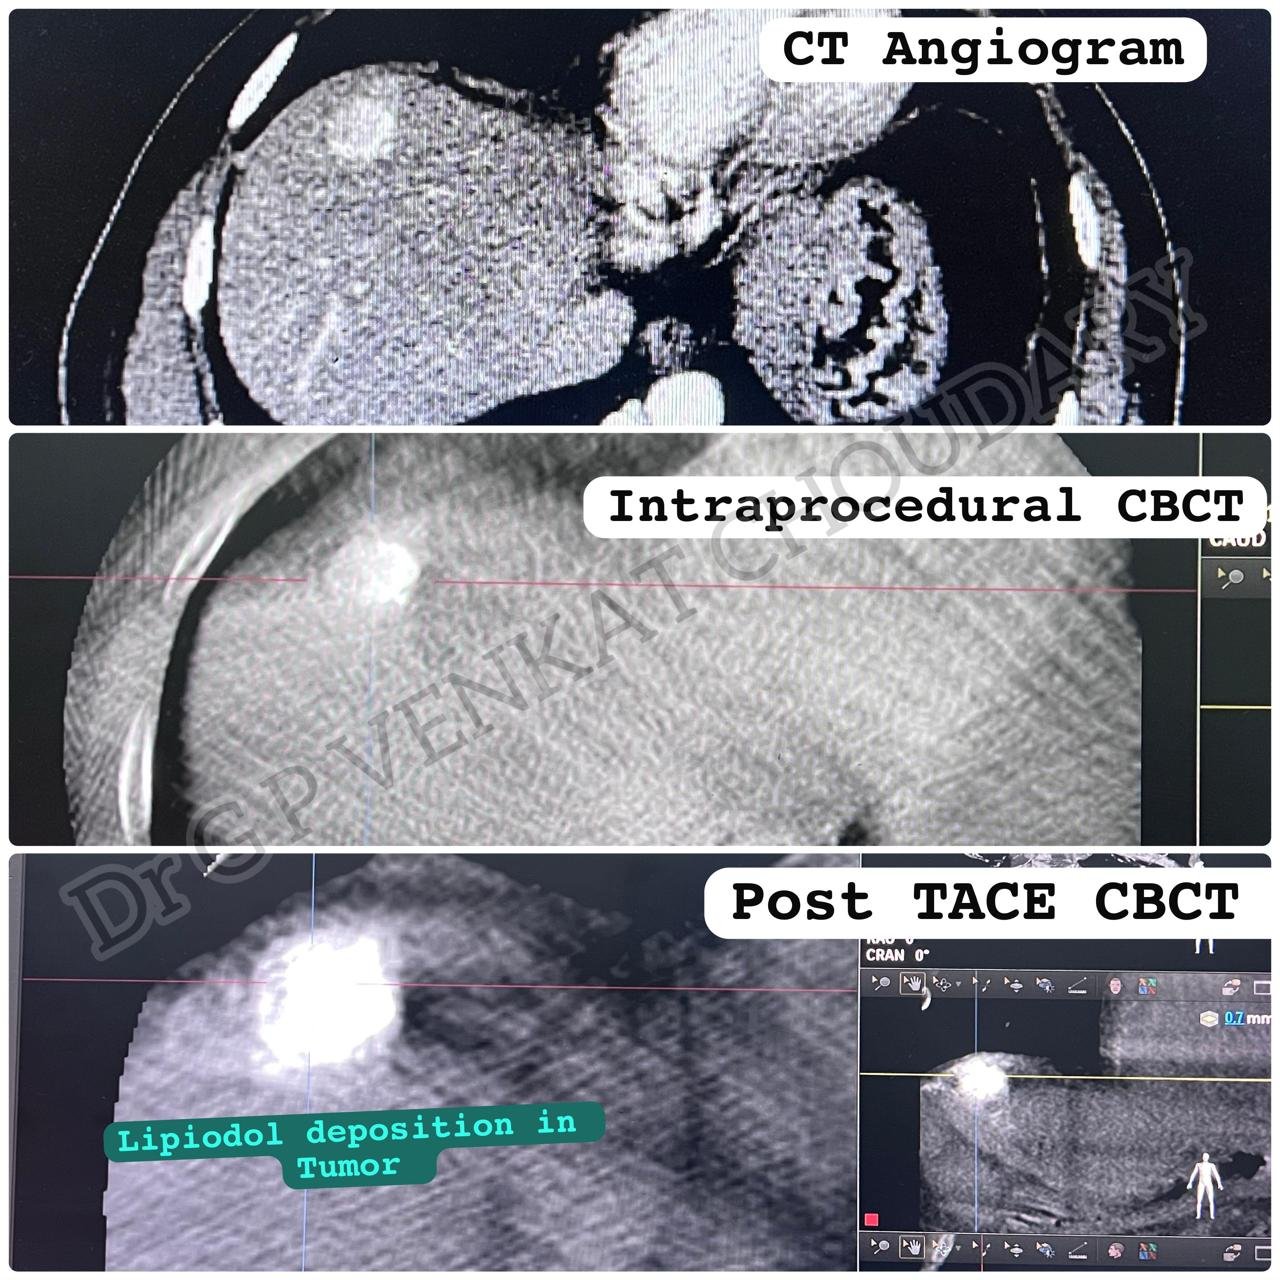

Oncological Interventions: TACE, TARE, Thermal Ablations, Liver Transplant Interventions